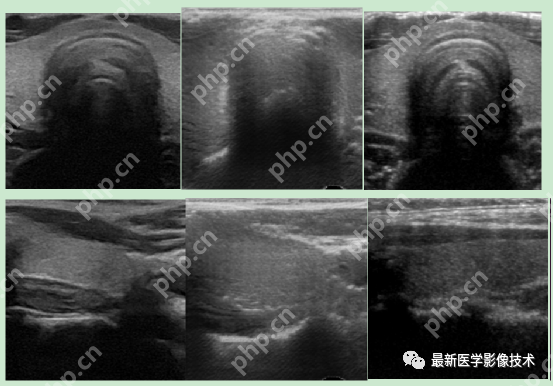

5、验证集部分生成结果

左图为低质量图像,中间为生成的高质量图像,右图为真实的高质量图像。

6、测试集部分生成结果

左图为低质量图像,右图为生成的高质量图像。